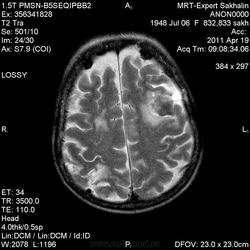

склоняюсь к кровизлиянию в левой теменной долей, начало перехода острой стадии в раннюю подострую( по периферии определяется повышение МРС по Т1 ВИ -метгемоглобин). Справа -старые кортикальные постишемческие глиозно-атрофические изменения. Контрастируется , вероятно за счет формирования участков ангионеогенза.

Это демиелинизирующий процесс, острая стадия, причем с геморрагическим пропитыванием в центре пораженных участков. В принципе, соответствует тяжелому рассеяному склерозу, хотя может быть и геморрагическая форма ОДЭМ. Также могут быть мозговые проявления системного васкулита: надо знать анамнез.

О.С., я согласен, что контрастирование нехарактерно для ОНМК, ведь в подострую стадию инфаркта наблюдается, как правило, гиральный тип усиления. Плюс, на ОНМК непохоже то, что поражено почти только белое вещество, а кора интактна. И потом, при такой локализации инфаркта обязательно должна быть яркая клиника, и уж никак не только "головная боль".

Скажите пожалуйста, а что с лобными полюсами полушарий?

Что касается лобных долей мне не хватает мр- изображения . Ну думаю это может быть связано с гиперостозом костей. Для уточнения можно назначить МСКТ.